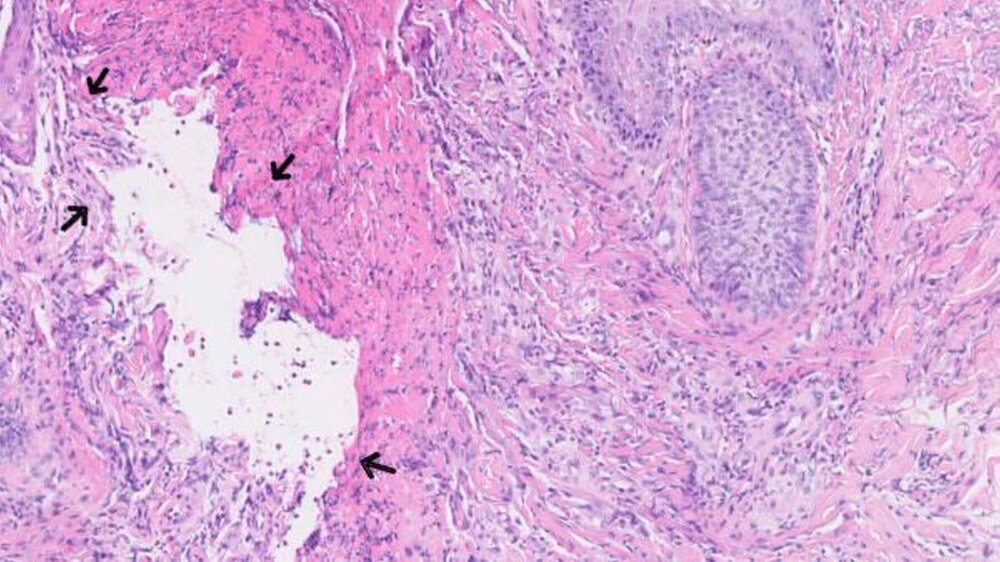

Mikroskopisch zeigten sich eine floride Ulzeration mit Fibrinexsudation und perivaskulären, entzündlichen Infiltraten mit neutrophilen Granulozyten sowie reaktive Veränderungen der Epidermis (Abbildungen 2 und 3). Auch bei einem erneuten Abstrich konnten keine Bakterien nachgewiesen werden.

Im Spätstadium zeigt sich histologisch eine Infiltration mit neutrophilen Granulozyten sowie Hämorrhagien [Su et al., 1986; Callen et al., 1998].